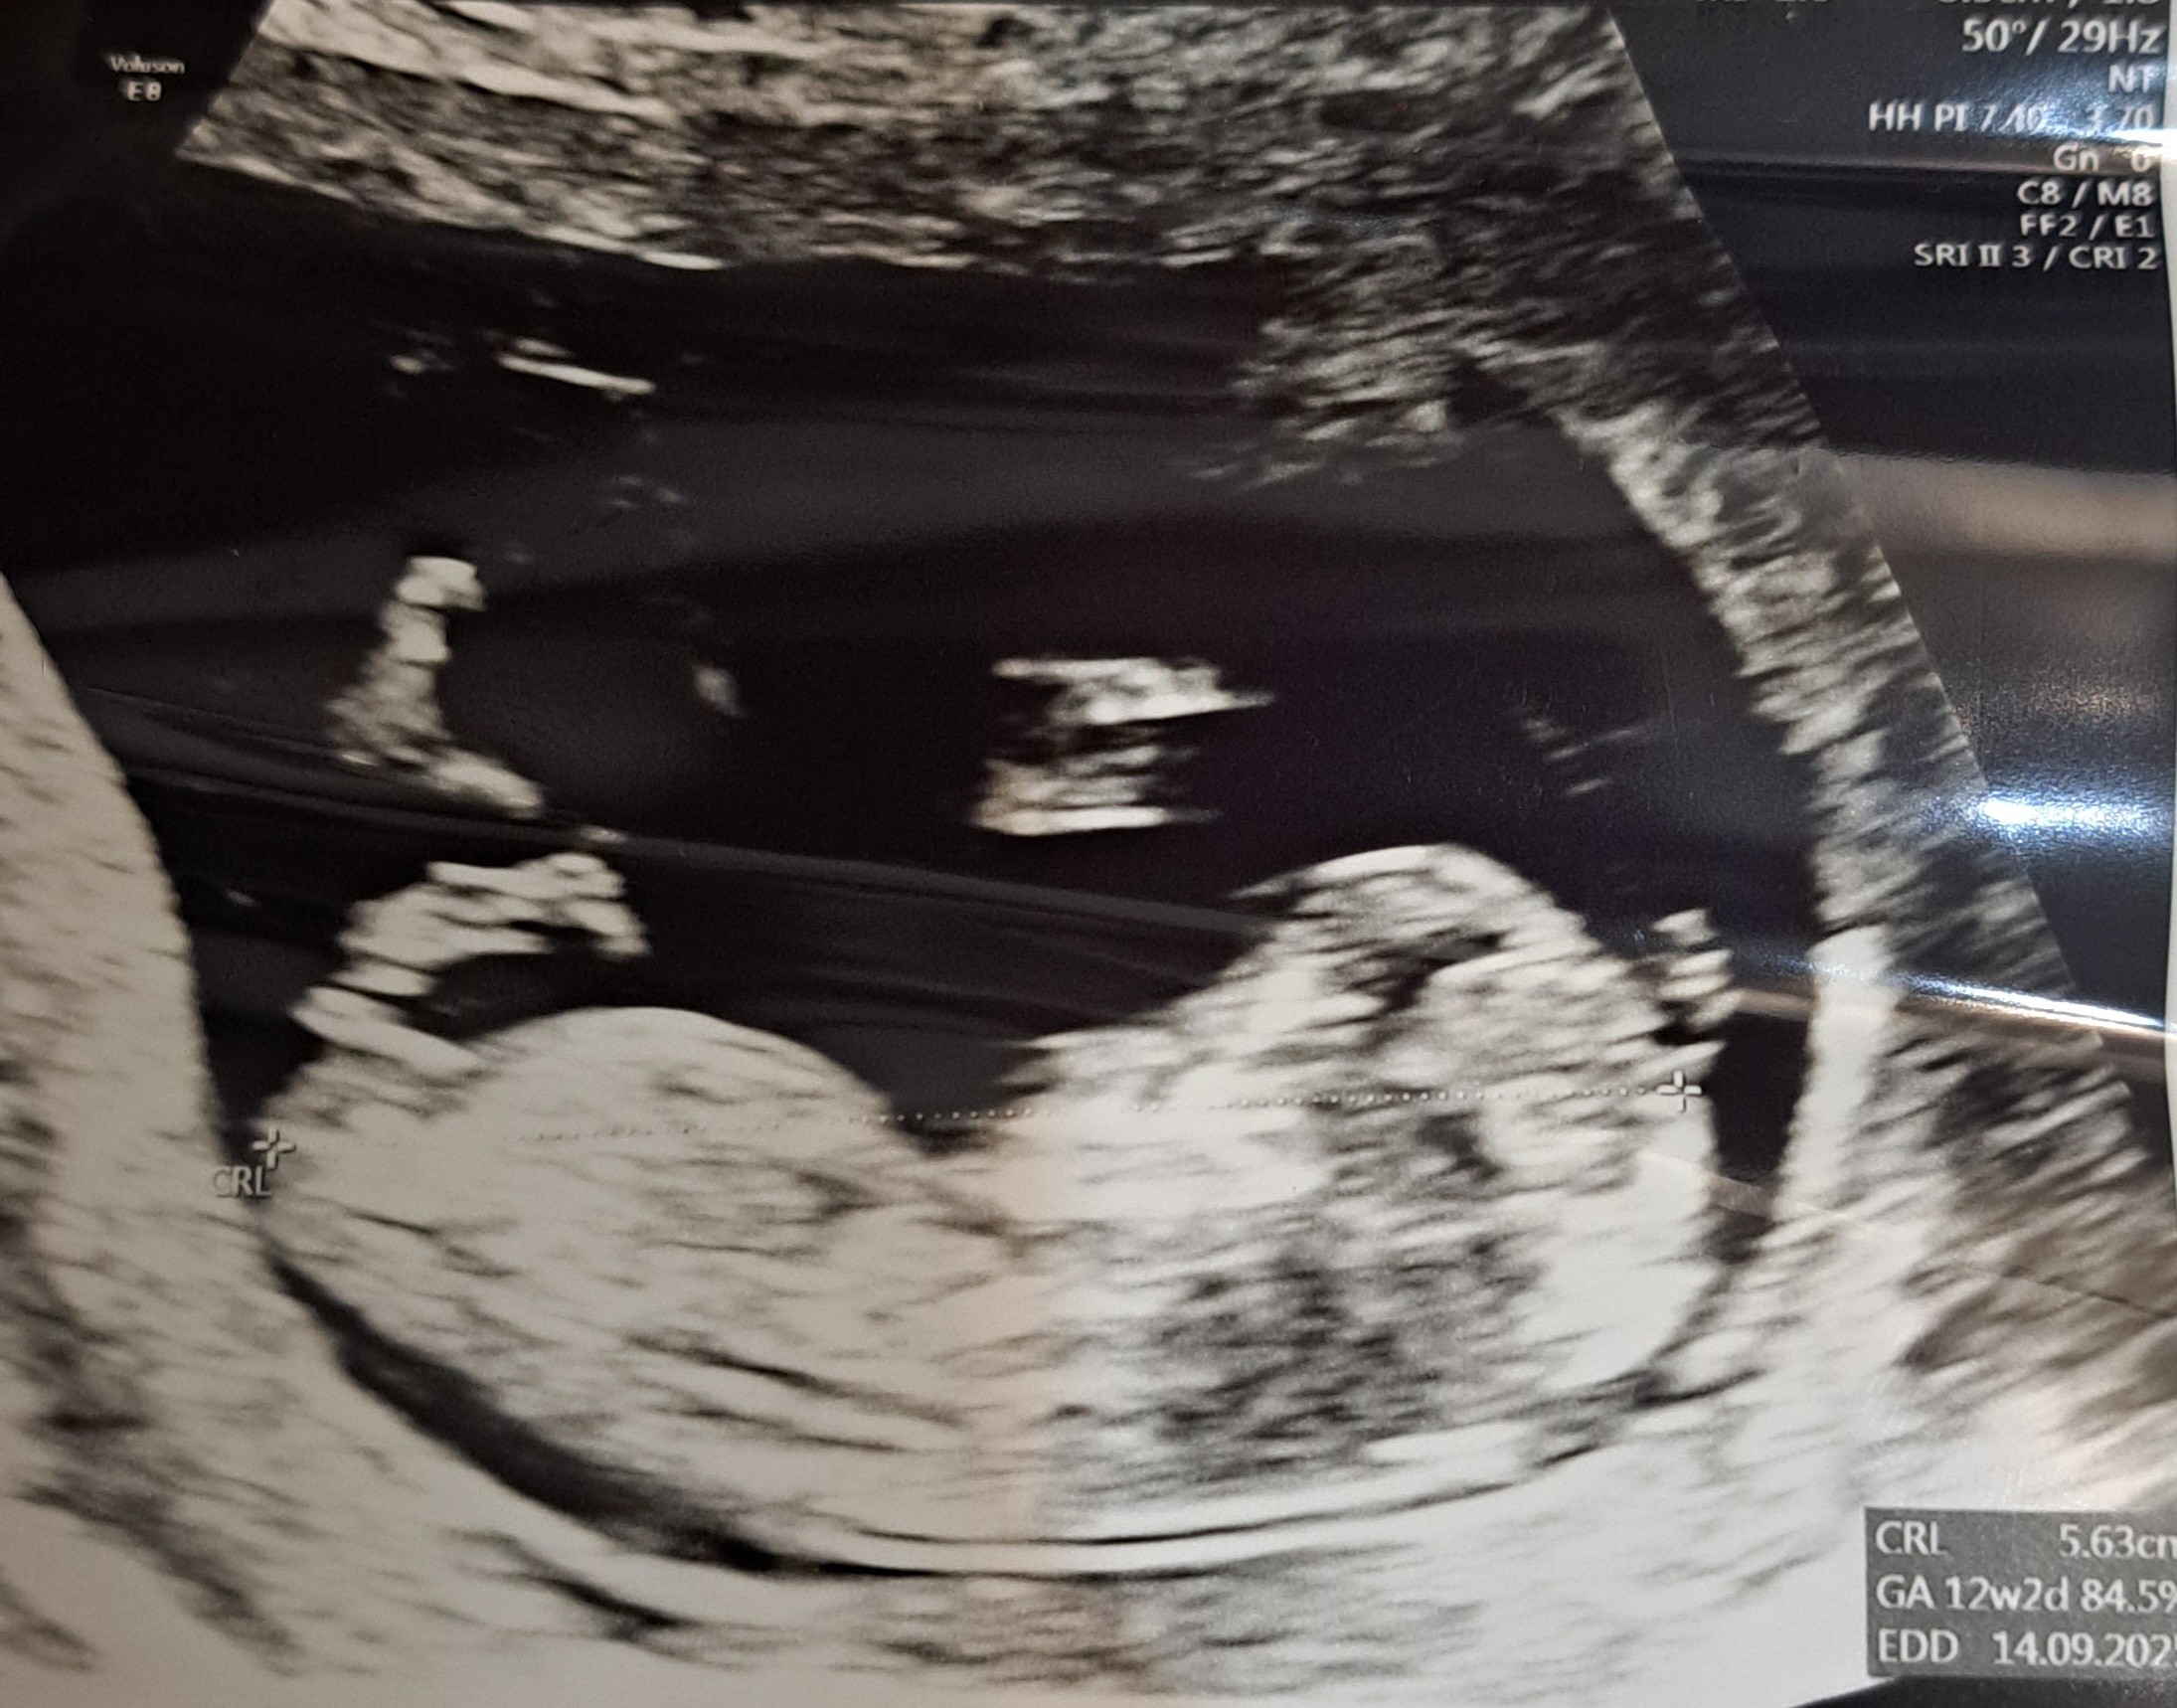

Witam przyszłe mamy, czy któraś z Was potrafi określić płeć dziecka po zdjęciu? Bardzo mi zależy ponieważ przygotwowujemu niespodziankę dla prababci :)

Dziękuję za odpowiedzi. Oczywiście pytałam lekarza ale w dniu badania nie chciał nam powiedzieć może nie był pewien albo się droczyl. Ja powiedziałam że jak mi powie w 12 tygodniu to pewnie jest pewien że chlopak. Na to lekarz że jak stoi to chlopak a jak lerzy dziewczynka po czym zrobił zdjęcie i kazał nam się zastanawiać ;) Na kolejnym usg tak się maluszek kręcił że nie dało się nic uchwycić.